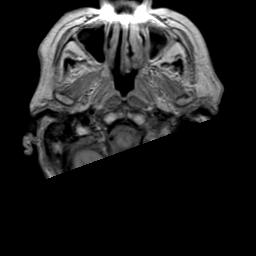

Meningioma, MR Study #2 -- Slice #0

[Home][Help][Clinical] Slice 0